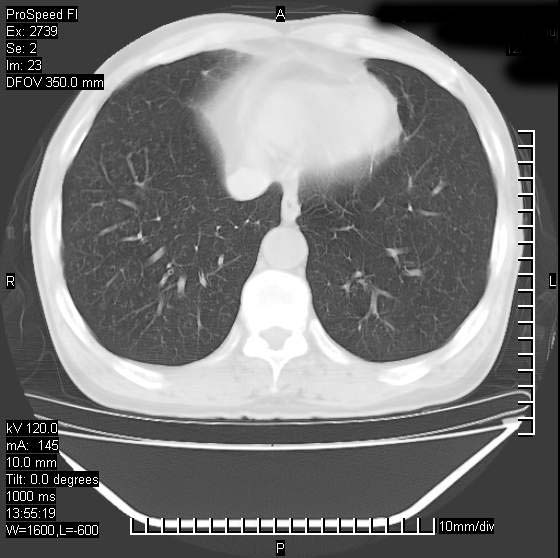

以下是引用andymaomao在2007-12-7 15:54:00的发言:[br]1.双上肺陈旧肺tb灶;[br]2.双中上肺矽肺;[br]3.双肺气肿;[br]4.图中箭头所指乃下腔静脉。

以下是引用山之魂海之韵在2007-12-7 18:59:00的发言:[br]支持矽肺,左肺上叶陈旧性结核,肺气肿。箭头所指乃下腔静脉。下腔静脉显影比主动脉显影迟,增强动脉后迟可以是不均匀的。

以下是引用chengjiaqiu1在2007-12-7 17:49:00的发言:[br]矽肺,左肺上叶陈旧性结核,肺气肿。中箭头所指乃下腔静脉。